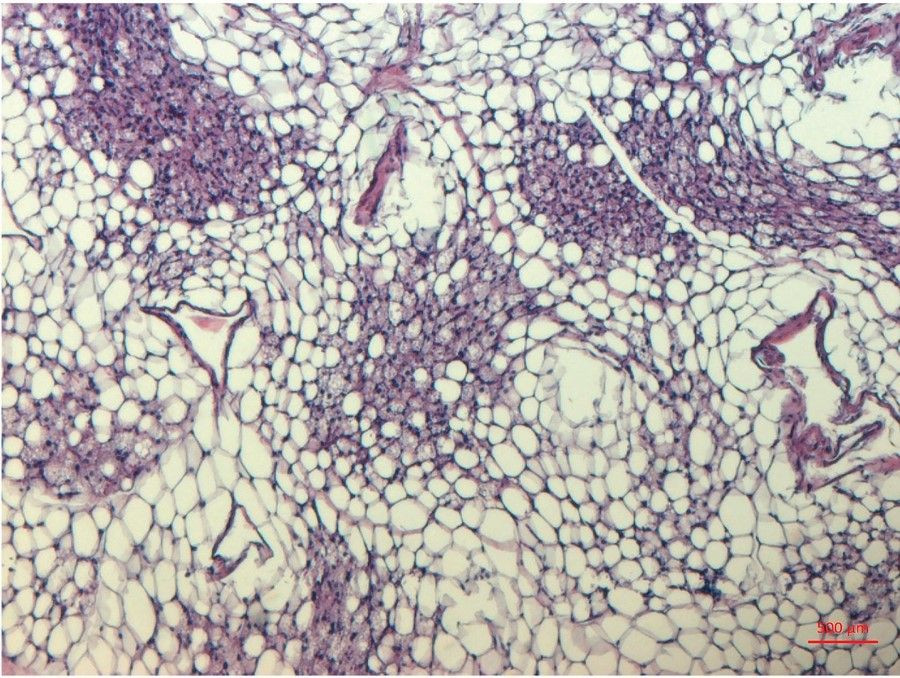

Es bien sabido que las células grasas pueden influir en la sensibilidad a la insulina. Ahora, investigadores del Instituto Karolinska, en Suecia, han descubierto que existen tres subtipos diferentes de células grasas maduras en el tejido adiposo blanco pero que sólo una de ellas, llamada AdipoPLIN, responde a la insulina. Los hallazgos, publicados en la revista `Cell Metabolism`, pueden ser relevantes para futuros tratamientos de enfermedades metabólicas como la diabetes de tipo 2, según los investigadores.

En el estudio los investigadores identificaron 18 clases de células que se agrupan en el tejido adiposo blanco de los humanos. De ellas, tres constituían células grasas maduras con fenotipos distintos.

En el estudio, el grupo de Rydén y Mejhert utilizó una técnica especial denominada transcriptómica espacial, desarrollada, entre otros, por el socio colaborador Patrik Stahl, profesor asociado del Real Instituto de Tecnología KTH y de SciLifeLab. La transcriptómica espacial genera información sobre la organización de los tejidos a través de la microscopía y la expresión de los genes mediante la secuenciación del ARN.